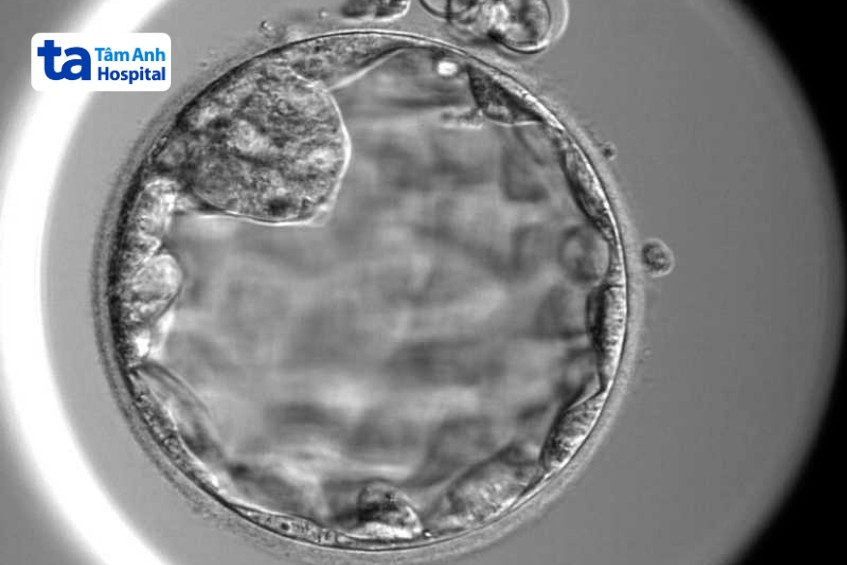

Phôi ngày 3 chỉ có từ 6-8 tế bào khó đánh giá được quá trình phát triển, khả năng bám dính làm tổ trong tử cung thấp hơn phôi ở giai đoạn ngày 5. Vợ chồng chị Thảo quyết định tiếp tục nuôi cấy phôi đến ngày 5. Kết quả hai phôi ngừng phát triển, còn một phôi vượt qua sàng lọc tự nhiên để đạt đến giai đoạn ngày 5, được phần mềm trí tuệ nhân tạo AI chấm điểm chất lượng phôi loại 3, mức độ trung bình.

“Chỉ những phôi khỏe mạnh, có khả năng phát triển tốt mới có thể phát triển đến giai đoạn phôi nang ngày 5. Người bệnh dù chỉ có một phôi, nhưng đây vẫn là cơ hội đáng quý để tăng tỷ lệ đậu thai.”, bác sĩ Thủy nói, cho biết thêm phôi được trữ đông chờ thời điểm lý tưởng để chuyển vào tử cung người bệnh.